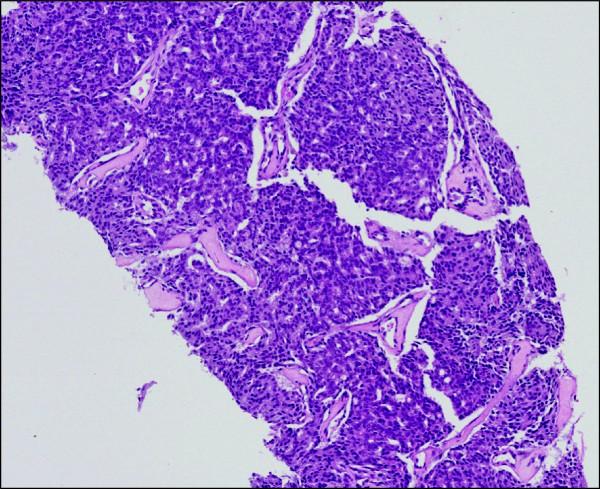

We present a case of a 72-year-old White man of British origin with metastatic castrate-resistant prostate cancer with bulky lymphadenopathy and a serum prostate-specific antigen of 295 μg/L. He received treatment with docetaxel chemotherapy plus prednisolone, but received just 3 cycles before treatment was stopped due to toxicity and lack of response (prostate-specific antigen was 276 μg/L 4 weeks after the last dose and there was a confirmed stable appearance on computed tomography scan). Unexpectedly, at follow-up 4 months later, the patient was clinically better; his prostate-specific antigen had dramatically improved to 4.1 μg/L and a re-staging computed tomography scan revealed complete resolution of his bulky lymphadenopathy. At the time, he was receiving a luteinising hormone-releasing hormone analogue but no other disease-modulating treatment. He remains well and asymptomatic, with his most recent serum prostate-specific antigen measuring 0.14 μg/L, 18 months after last receiving chemotherapy.

我们报告一例72岁、祖籍英国的白人男性,患有转移性去势抵抗性前列腺癌,伴有巨大淋巴结病,血清前列腺特异性抗原为295μg/L。他接受了多西他赛化疗加泼尼松龙治疗,但由于毒性反应和缺乏疗效(最后一剂后4周前列腺特异性抗原为276μg/L,计算机断层扫描显示外观稳定),仅接受了3个周期的治疗就停止了。出乎意料的是,4个月后的随访中,患者临床症状改善;他的前列腺特异性抗原显著改善至4.1μg/L,重新分期的计算机断层扫描显示其巨大淋巴结病完全消退。当时,他正在接受促黄体生成素释放激素类似物治疗,但未接受其他疾病调节治疗。在最后一次接受化疗18个月后,他仍然状况良好且无症状,其最近的血清前列腺特异性抗原测量值为0.14μg/L。